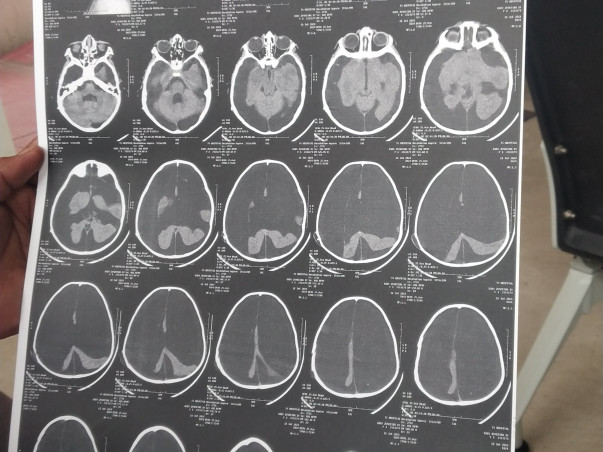

But when Chutki turned 5 months old, she had her first seizure. 2 days later, when she got a fever, we rushed her to the hospital. The doctor performed few tests and prescribed medicines. For weeks we kept going to the hospital, but Chutki did not become well. Almost three weeks later after one of the doctors suggested that we get an MRI, the report showed that she had some fluid in her brain that needed to be drained. The procedure would take a lot of money but we did not have the enough money.

She has fluids in her brain which need to be operated through shunt, but it is bulging and required for further treatment. We are in need of approximately 10 lakhs funds, which is not a small amount. As a mother, I want to see my Chutki laugh, talk and play. She is just 2.2 year old and deserves a healthy and happy life. And I believe this can happen with all of your support.